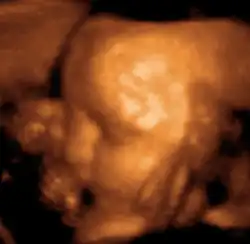

Акушерство, гинекология и пренатальная диагностика

Ультразвуковое исследование используется для изучения внутренних половых органов женщины, состояния беременной матки, анатомии и мониторинга внутриутробного развития плода.

Этот эффект широко применяется в акушерстве, так как звуки, идущие от матки, легко регистрируются. На ранней стадии беременности звук проходит через мочевой пузырь. Когда матка наполняется жидкостью, она сама начинает проводить звук. Положение плаценты определяется по звукам протекающей через неё крови, а через 9 — 10 недель с момента образования плода прослушивается биение его сердца. С помощью ультразвукового исследования можно также определять количество зародышей или констатировать смерть плода.

Уже с третьей недели от момента зачатия можно увидеть эхонегативное образование плодного яйца диаметром 5—6 мм в полости матки. С 4—5 недель возможна визуализация эмбриона в виде эхопозитивной полоски размером 6—7 мм. Головка эмбриона становится видимой как отдельное анатомическое образование средним диаметром 10—11 мм на 8—9 неделе[8].